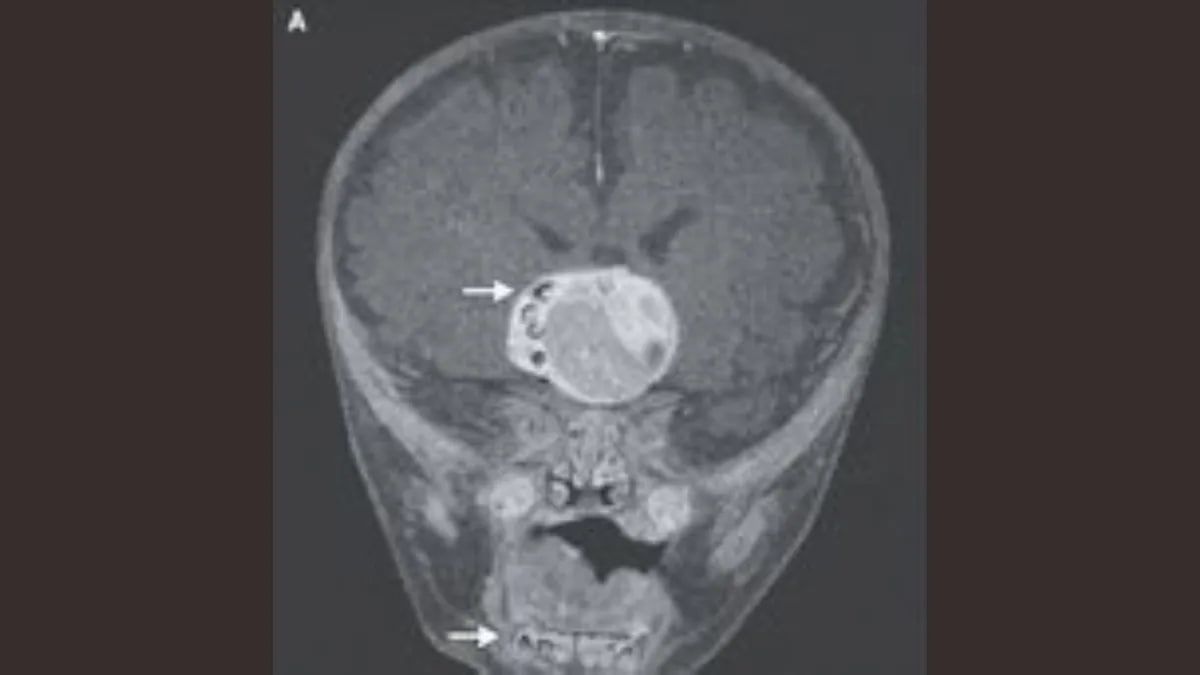

Четырехмесячного мальчика отвезли на медицинское обследование, поскольку его голова росла быстрее, чем это было нормально для его возраста. Сканирование мозга подтвердило, что у него опухоль головного мозга. Однако, согласно отчету о случае, во время операции на головном мозге по удалению опухоли врачи обнаружили, что она содержала несколько полностью сформировавшихся зубов.

Выяснилось, что у ребенка краниофарингиома - редкая разновидность доброкачественной опухоли головного мозга. После операции его врач сказал, что мальчик "чувствует себя очень хорошо, учитывая все обстоятельства".